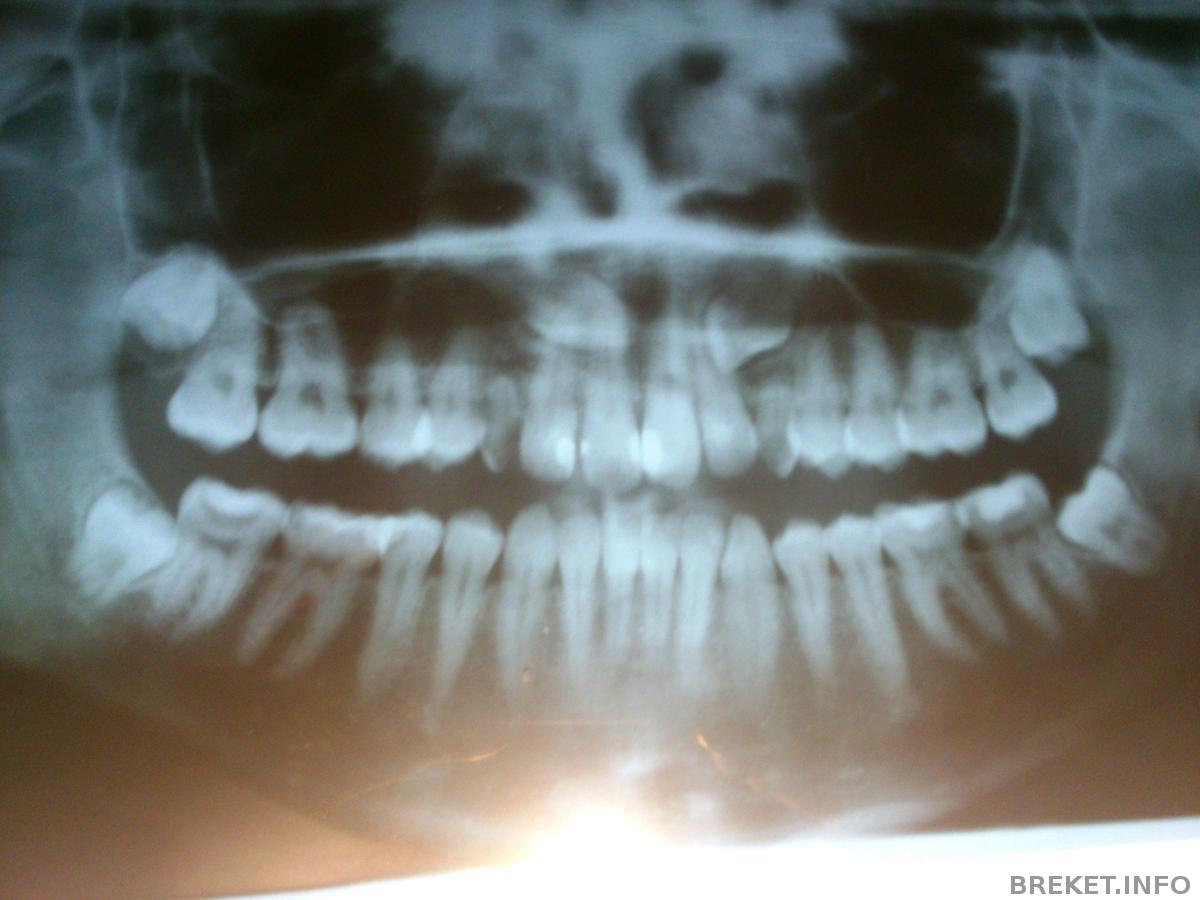

Dunaeva, мне до снимков тоже говорили мол 1,5-2, а вот после снимков сказали что 3-4 ((( у меня случай тяжёлый могу снимок позже панорамный приложить, если интересно конечно

Алла Ми, я бы посмотрела, мне очень интересно.